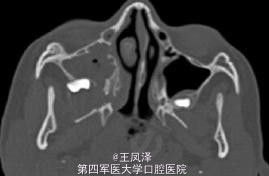

患者女,9 岁,发现右侧上颌骨无痛性肿块 3 个月余。查体见右侧上颌骨明显肿胀,质硬,不可活动,触之无疼痛感,约 3 cm× 2 cm 大小。肿块自右侧颊部向右侧腭部膨隆,右侧上颌牙齿移位,I 度松动。余未见明显异常